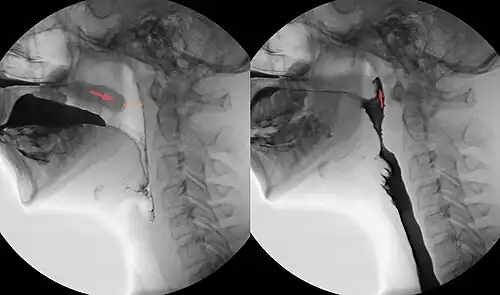

Zur orientierenden Untersuchung des velopharyngealen Verschlusses reicht eine Sprechprobe. Der Patient kann bei insuffizientem Verschluss den Verschlusslaut [k] nicht aussprechen. Statt „Kartoffeln im Keller“ sagt er dann „Gartoffeln im Geller“ und seine Sprache ist insgesamt schwer verständlich. Außerdem haben die Patienten Probleme mit den Öffnungs- und Verschlussbewegungen im velopharyngealen Bereich beim Übergang von Vokalen zu Konsonanten und umgekehrt. Für genauere klinische und experimentelle Untersuchungen wurden verschiedenste Messgeräte zur oronasalen Druckmessung und Aufzeichnung ersonnen, die unter anderem für die Beurteilung des Operationserfolges nach den verschiedenen Operationstechniken erforderlich sind. Insgesamt sind jedoch die quantitativen Erfassungsmethoden (z. B. intraorale Druckmessung; velopharyngeale Funktionsdiagnostik mit elektromagnetischer Artikulographie; aerodynamische Messungen durch Pressure-Flow-Verfahren; Druckdifferenzmessung; Sonogramm) noch nicht ausgereift und bleiben wegen des großen apparativen Aufwandes Therapiestudien vorbehalten. Die endoskopische Beurteilung der VPI, insbesondere die endoskopischen Videoaufzeichnungen von Sprechproben, ist eine Standardmethode. Weiterhin gibt es die Beurteilung mit einem flexiblen Nasopharyngoskop und die flexible Videonasopharyngoskopie.